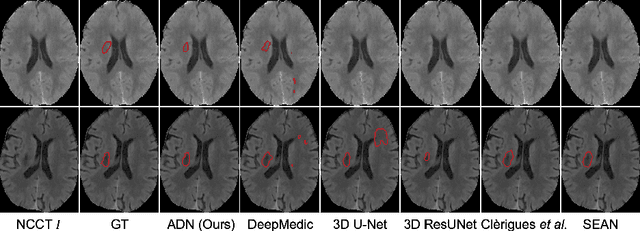

Abstract:Accurate infarct segmentation in non-contrast CT (NCCT) images is a crucial step toward computer-aided acute ischemic stroke (AIS) assessment. In clinical practice, bilateral symmetric comparison of brain hemispheres is usually used to locate pathological abnormalities. Recent research has explored asymmetries to assist with AIS segmentation. However, most previous symmetry-based work mixed different types of asymmetries when evaluating their contribution to AIS. In this paper, we propose a novel Asymmetry Disentanglement Network (ADN) to automatically separate pathological asymmetries and intrinsic anatomical asymmetries in NCCTs for more effective and interpretable AIS segmentation. ADN first performs asymmetry disentanglement based on input NCCTs, which produces different types of 3D asymmetry maps. Then a synthetic, intrinsic-asymmetry-compensated and pathology-asymmetry-salient NCCT volume is generated and later used as input to a segmentation network. The training of ADN incorporates domain knowledge and adopts a tissue-type aware regularization loss function to encourage clinically-meaningful pathological asymmetry extraction. Coupled with an unsupervised 3D transformation network, ADN achieves state-of-the-art AIS segmentation performance on a public NCCT dataset. In addition to the superior performance, we believe the learned clinically-interpretable asymmetry maps can also provide insights towards a better understanding of AIS assessment. Our code is available at https://github.com/nihaomiao/MICCAI22_ADN.